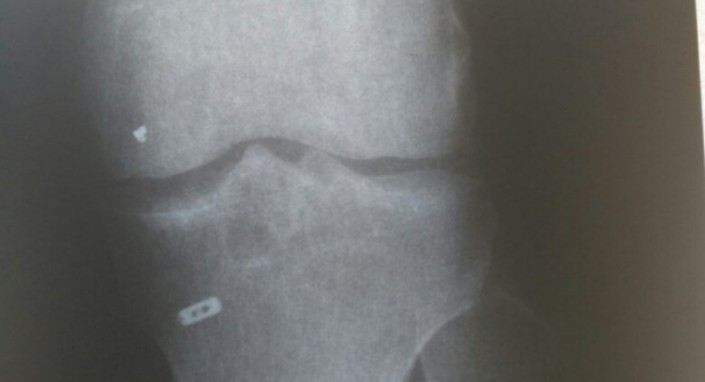

"У него боли не прекращались, даже судороги были. Он думал, что это постреабилитационный период, что это естественное явление, что нога, наверное, заживает. Спустя год он сделал МРТ, которое показало, что в колене есть инородный предмет. Мы сразу обратились в клинику за разъяснениями, они сказали, что, возможно, это часть металлического инструмента", - рассказал адвокат Нариман Закирьянов.

"Эта железка до сих пор в ноге. Операция дорогостоящая, она стоит за рубежом порядка 10 тысяч долларов. У него средств не было, соответственно, мы требовали эту сумму с клиники. Он не требует деньги в корыстных целях, мы требовали деньги на операцию, чтобы этот предмет удалить", - отметил адвокат.